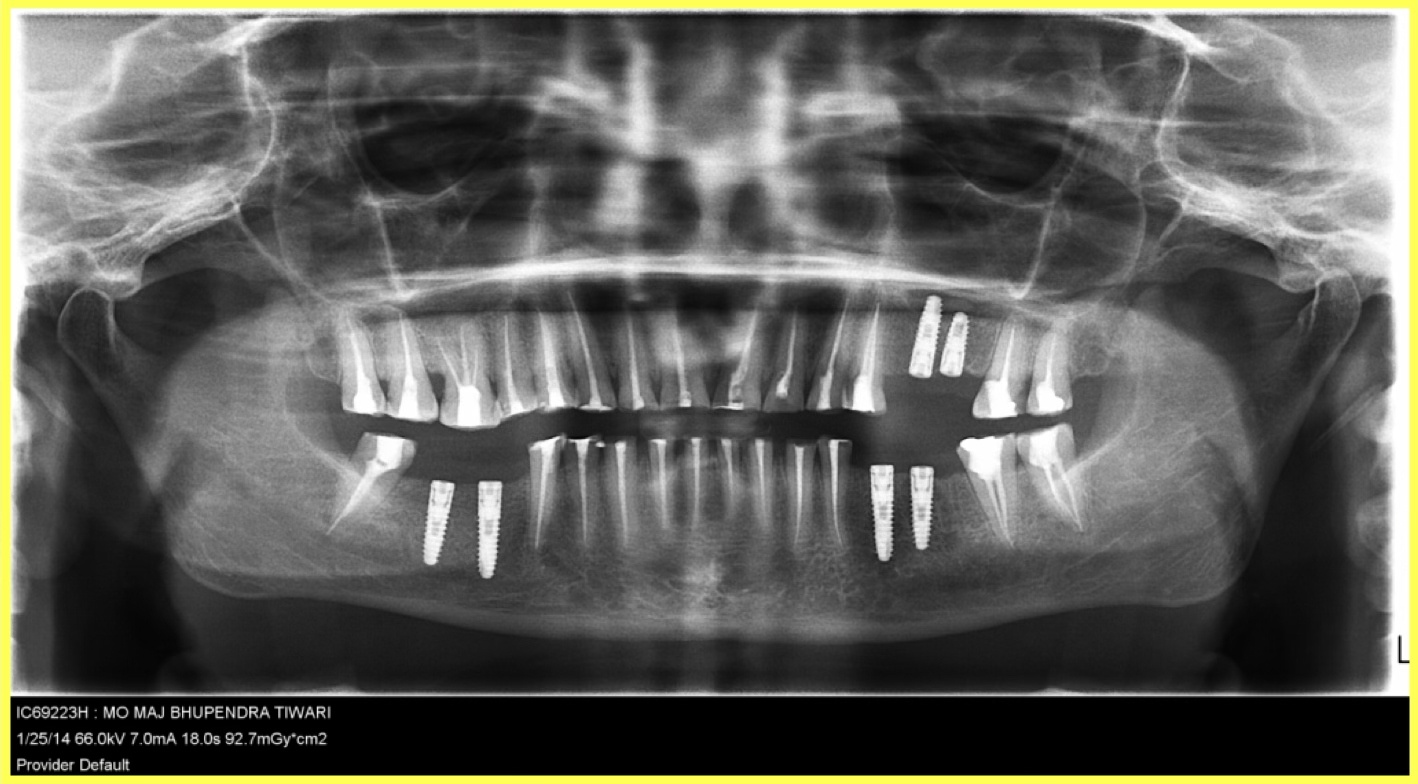

Strategic placement of 6 Dio dental implants in the regions of missing teeth using precise surgical protocols.

Root canal treatment performed on all remaining attrited teeth to ensure long-term viability before crown placement.

Temporary crowns were cemented to protect prepared teeth and maintain function during healing period.